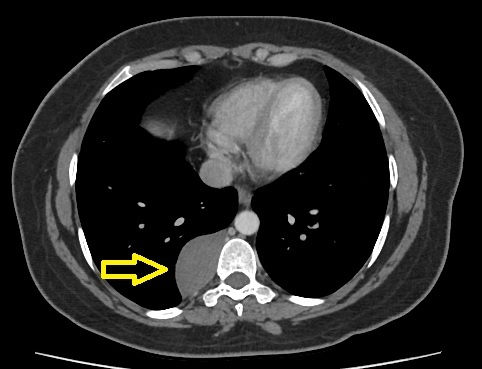

Образование заднего средостения

Образования заднего средостения — это патологические структуры, возникающие в задней части средостения, т.е. за условной плоскостью, проведенной через трахею и корни легких.

Они могут быть доброкачественными или злокачественными, врожденными или приобретенными.

Чаще всего в заднем средостении располагаются:

4. Сосудистые патологии:

• Аневризмы грудной аорты.

• Расслоение аорты.

2. КТ с контрастом: оценка структуры, связи с сосудами и органами.